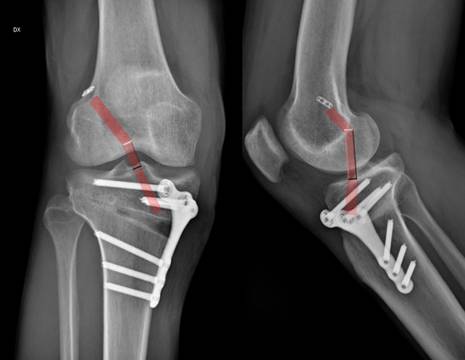

L'osteotomia tibiale valgizzante è un intervento di riallineamento degli arti destinato a pazienti con artrosi nel compartimento mediale del ginocchio e che non sono candidati idonei per un intervento di protesi al ginocchio, a causa della malattia meno grave, dell’età più giovane e delle maggiori esigenze fisiche. L'intervento di osteotomia tibiale valgizzante, correggendo l'asse di carico dell'arto, sfrutta il compartimento ancora sano del ginocchio prevenendo un'artrosi maggiore.

La tibia è esposta e parzialmente sezionata sotto controllo radiografico (Figura 3). La correzione dell’asse tibiale è effettuata sezionando la tibia alla sua porzione prossimale e modificandone l’asse.

Il grado di correzione è calcolato in base alla deformità iniziale valutata con una radiografia preoperatoria (Figura 5). Una placca metallica permette poi il mantenimento della correzione ottenuta (Figura 4). A volte è necessario colmare il difetto che si ottiene con la correzione, per favorire il consolidamento dell’osso (Figura 4).